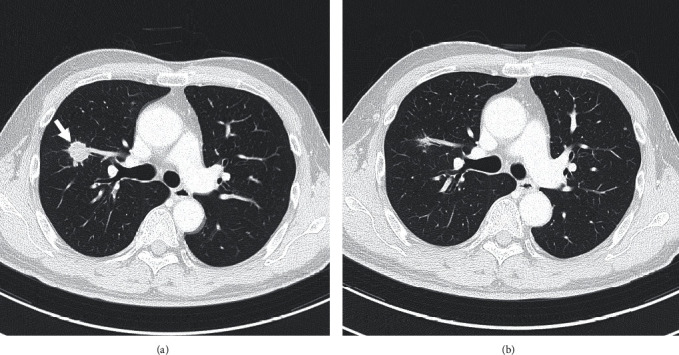

A 64-year-old man was diagnosed with invasive bladder and right lower ureteral urothelial cancer with right pelvic lymph node and lung metastases. He received four courses of gemcitabine and cisplatin therapy. He underwent lung metastasectomy and radical cystoprostatectomy, with not only primary lesions but also metastatic lesions showing a complete response. New multiple lung metastases were revealed five months after adjuvant chemotherapy. On starting pembrolizumab therapy, the metastatic lesions are notably reduced in size. He is currently receiving pembrolizumab therapy, and no recurrence has been observed for over one year.

Abstract Image